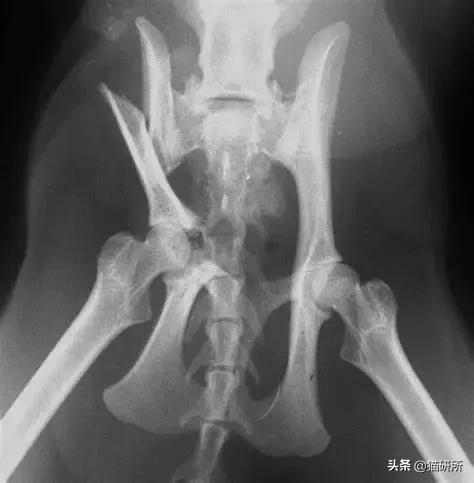

骨盆骨折

猫第二常见的骨折,骨折病例中约25%的病例是盆骨骨折。

最常见的原因包括高处坠落和车辆创伤。

当猫咪盆骨骨折时,除运动异常外,需要注意猫咪是否出现神经功能损伤,排尿排便功能是否正常。

图自:猫研所动物医院